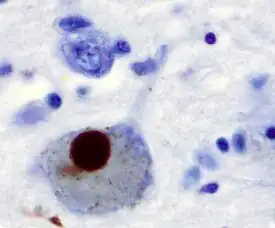

In Parkinson's disease and other synucleinopathies, insoluble forms of alpha-synuclein accumulate as inclusions in Lewy bodies.[11]

Alpha synuclein, having no single, well-defined tertiary structure, is an intrinsically disordered protein,[79][80] with a pI value of 4.7,[81] which, under certain pathological conditions, can misfold in a way that exposes its core hydrophobic residues to the intracellular milieu, thus providing the opportunity for hydrophobic interactions to occur with a similar, equally exposed protein.[80] This could lead to self assembly and subsequent aggregation into large, insoluble fibrils known as amyloids.[80] The conversion of soluble alpha synuclein into highly ordered, cross-β sheet, fibrillar structures does not, as previously thought, follow a two-step mechanism, rather, occurs through a series of transient, soluble oligomeric intermediates.[82][83] In 2011, two groups published their findings that unmutated α-synuclein forms a stably folded tetramer that resists aggregation, asserting that this folded tetramer represented the relevant in vivo structure in cells,[84][85] thereby relieving alpha synuclein of its disordered status. Proponents of the tetramer hypothesis argued that in vivo cross-linking in bacteria, primary neurons and human erythroleukemia cells confirmed the presence of labile, tetrameric species.[86][87][88] However, despite numerous in-cell NMR reports demonstrating that alpha synuclein is indeed monomeric and disordered in intact E. coli cells,[89][90][91][92][93][94][95][96] it is still a matter of debate in the field despite an ever growing mountain of conflicting reports.[93][97][98] Nevertheless, alpha-synuclein aggregates to form insoluble fibrils in pathological conditions characterized by Lewy bodies, such as Parkinson's disease, dementia with Lewy bodies and multiple system atrophy.[99][100] These disorders are known as synucleinopathies. In vitro models of synucleinopathies revealed that aggregation of alpha-synuclein may lead to various cellular disorders including microtubule impairment, synaptic and mitochondrial dysfunctions, oxidative stress as well as dysregulation of Calcium signaling, proteasomal and lysosomal pathway.[101] Alpha-synuclein is the primary structural component of Lewy body fibrils. Occasionally, Lewy bodies contain tau protein;[102] however, alpha-synuclein and tau constitute two distinctive subsets of filaments in the same inclusion bodies.[103] Alpha-synuclein pathology is also found in both sporadic and familial cases with Alzheimer's disease.[104]

Antibodies against alpha-synuclein have replaced antibodies against ubiquitin as the gold standard for immunostaining of Lewy bodies.[129] The central panel in the figure to the right shows the major pathway for protein aggregation. Monomeric α-synuclein is natively unfolded in solution but can also bind to membranes in an α-helical form. It seems likely that these two species exist in equilibrium within the cell, although this is unproven. From in vitro work, it is clear that unfolded monomer can aggregate first into small oligomeric species that can be stabilized by β-sheet-like interactions and then into higher molecular weight insoluble fibrils. In a cellular context, there is some evidence that the presence of lipids can promote oligomer formation: α-synuclein can also form annular, pore-like structures that interact with membranes. The deposition of α-synuclein into pathological structures such as Lewy bodies is probably a late event that occurs in some neurons. On the left hand side are some of the known modifiers of this process. Electrical activity in neurons changes the association of α-synuclein with vesicles and may also stimulate polo-like kinase 2 (PLK2), which has been shown to phosphorylate α-synuclein at Ser129. Other kinases have also been proposed to be involved. As well as phosphorylation, truncation through proteases such as calpains, and nitration, probably through nitric oxide (NO) or other reactive nitrogen species that are present during inflammation, all modify synuclein such that it has a higher tendency to aggregate. The addition of ubiquitin (shown as a black spot) to Lewy bodies is probably a secondary process to deposition. On the right are some of the proposed cellular targets for α-synuclein mediated toxicity, which include (from top to bottom) ER-golgi transport, synaptic vesicles, mitochondria and lysosomes and other proteolytic machinery. In each of these cases, it is proposed that α-synuclein has detrimental effects, listed below each arrow, although at this time it is not clear if any of these are either necessary or sufficient for toxicity in neurons.